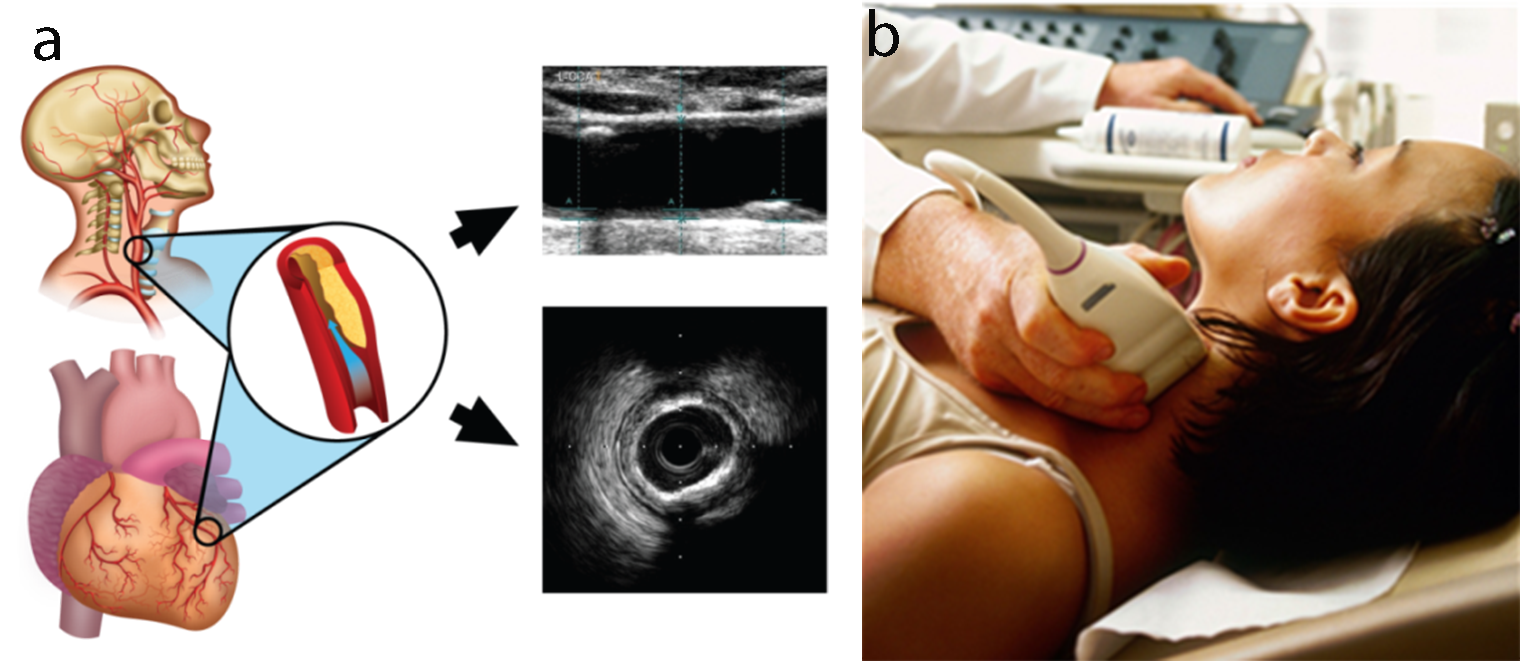

Carotid B-mode ultrasound (BMUS) is a comparatively less expensive and user-friendly imaging modality [4, 28, 123, 124, 125, 126]. Therefore, it has a wide scope to be used for routine preventive screening of atherosclerotic plaque and CVD risk assessment [51, 70, 123, 127, 128, 129, 130]. Automated systems have been well developed for image phenotype measurements [131, 132, 133, 134] and validated using CT, MRI, and the gold standard [135, 136]. Recent studies have demonstrated the ability of carotid ultrasound image-based phenotypes such as carotid intima-media thickness (in common carotid or bulb region [137]), total carotid plaque area, carotid intima-media thickness variability (cIMTV) [138], maximum plaque height [139], and morphology of the plaque play a vital role in the prediction of risk of CVE [31, 70, 128, 140, 141]. Studies have also indicated that these carotid image-based phenotypes when combined with traditional cardiovascular risk factors have improved in their prediction ability [70, 128, 129]. Several studies have indicated an annual progression of cIMT and carotid plaque with the traditional risk factors [142, 143, 144, 145, 146].

Recently some efforts were made to integrate the traditional risk factors with the carotid ultrasound image-based phenotypes such as cIMT and plaque area [28, 48, 70, 129]. cIMT and plaque area capture the morphological plaque variations and are considered as the surrogate biomarkers of coronary artery disease (Fig. 8). Therefore, when such an integrated approach was compared against the CCVRC, it reported improved risk stratification.

Fig. 8.

Fig. 8.Carotid ultrasound imaging for preventive CVD risk screening. (a) Carotid artery being used as a surrogate marker for coronary artery. (b) Imaging device.